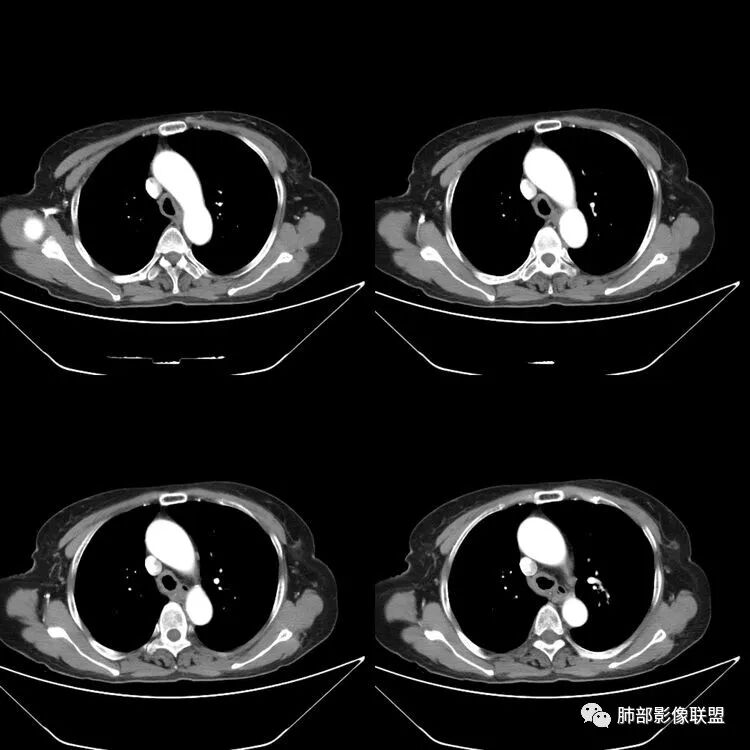

患者,女,64岁,反复咳嗽、咳痰、胸闷10年,加重2周患者10余年来每当受凉感冒出现咳嗽、咳痰、胸闷,有时痰中带血,输液治疗(具体不详)可好转。既往有声带肥厚手术病史。CT示气管、主支气管及分支支气管管壁弥漫性增厚累及膜部,局部伴钙化,管腔狭窄,考虑淀粉样变性

患者,女,64岁,反复咳嗽、咳痰、胸闷10年,加重2周。气管支气管及两肺下叶 支气管弥漫性的环状增厚,管腔扩张,管腔感觉比较松弛。第一感觉,气管支气管淀粉样变。鉴别诊断,1、支气管内膜结核,肺内散在一些支气管的播散病灶,粟粒结节为主,形态比较单一。2、复发性的多软骨炎,就得了解一下其他部位,有没有多个部位的软骨炎。这个病人右侧胸廓缩小,升主动脉明显的扩张,其横径明显的超过了降主动脉。

征象很明确

弥漫支气管壁增厚,膜部受累

声带肥厚——受累

隐约见钙化

南边:肺部有肺气肿支气管腔狭窄淀粉样变性?复发性多软骨炎?血管炎?慢支?结核?曲霉菌?南边:一般还是淀粉样变性与复发性多软骨炎鉴别其次就是支气管骨化症,但是骨化下朝上,且壁结节状钙化明显,本例不太支持。至于结核、曲霉菌?1.结核,一般不会这么广泛,支气管壁狭窄后扩张2.曲霉菌可以这么广泛,但是支气管壁管腔扩张,而且附近脂肪间隙有炎性反应,不太支持;3.血管炎,一般合并肺内有病灶,但是声带受累,放待排;4.软骨炎一般全身受累,例如耳廓等;而且膜部不受累,不太支持;倾向于淀粉样变性;淀粉分很多型,气管支气管是最常见的。尘缘:影像上生理性钙化与支气管骨化无法区别,镜检也不好鉴别,需要依赖活检,看粘膜中是否合并炎性改变(淋巴细胞,组织细胞等炎性细胞侵润)来鉴别Coke with ice:经常看到的这种是老年性肺改变,又称年龄相关肺改变。气管和支气管弥漫性软骨钙化,常见老年女性。尘缘:支气管骨化症很罕见的,所以绝大多数还是生理性钙化。对于老年人,无临床症状的钙化,还是基本上都是生理性钙化,无临床意义。大雄:如果管壁钙化伴明显增厚 影像还是提示一下建议支气管镜稳妥些